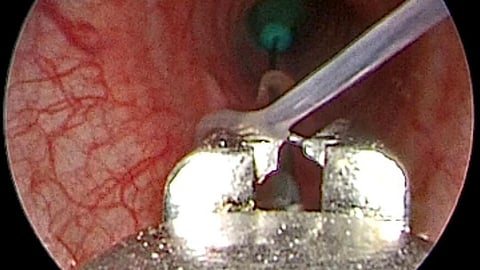

இதைத் தொடர்ந்து OGD ஸ்கோபி செய்யப்பட்டு, உணவுக்குழாயில் ஊசி இல்லை என்று தெரிவிக்கப்பட்டது. இதையடுத்து மார்புடன் கூடிய CT கழுத்து எடுக்கப்பட்டு, மூச்சுக்குழாயில் ஊசி இருப்பது உறுதி செய்யப்பட்டது.

இதையடுத்து மறுநாள் 06ம் தேதி காலை மயக்க மருந்தின் கீழ் RIGID பிராங்கோ ஸ்கோபியை பயன்படுத்தி ஊசி அகற்றப்பட்டது.